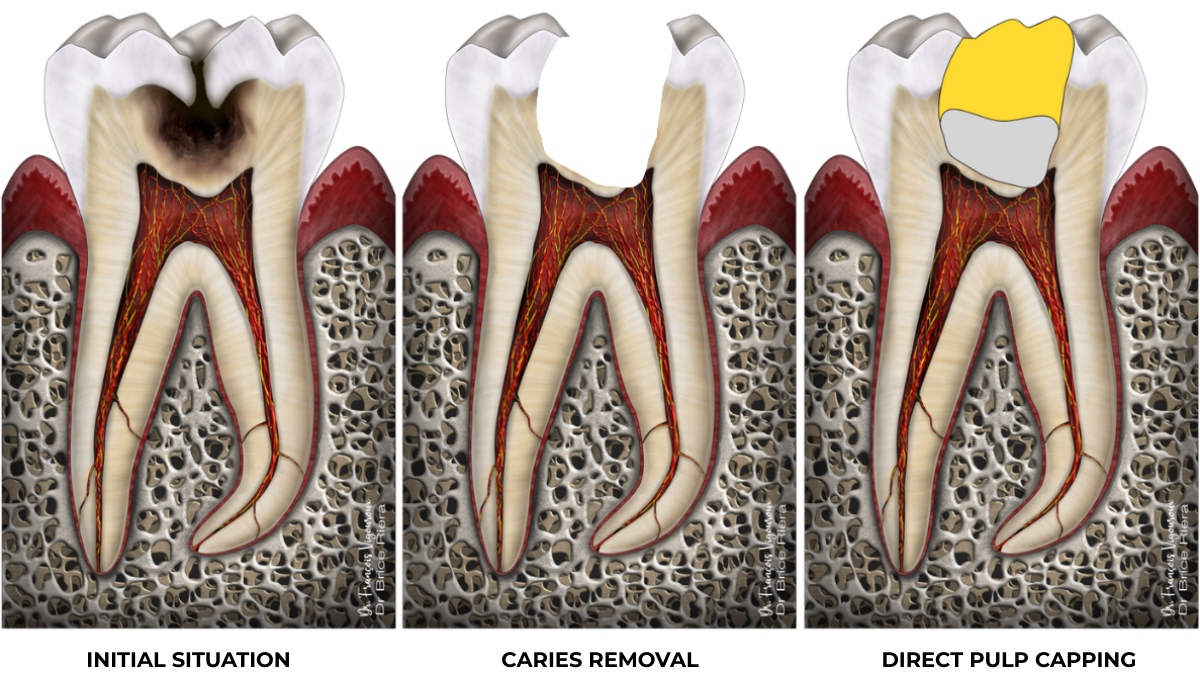

Partial pulpotomy

Sometimes it is necessary to go deliberately a little further into the pulp. This is the case when haemostasis cannot be achieved, or when a minimal form of containment is needed to hold the bioactive biomaterial in place.

Clinical case

Partial pulpotomy: 88.2% success rate